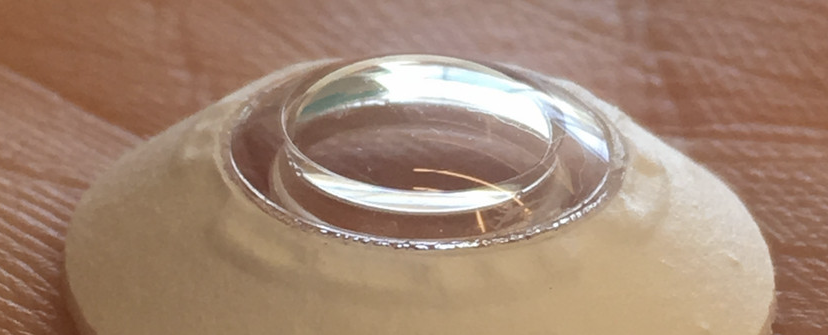

Ένας 78χρονος άντρας ξανα βρήκε την όρασή του αφού ήταν ο πρώτος ασθενής που έλαβε ένα πολλά υποσχόμενο νέο είδος εμφυτεύματος κερατοειδούς. Αναπτύχθηκε από μια εταιρεία που ονομάζεται CorNeat , το KPro είναι το πρώτο εμφύτευμα που μπορεί να ενσωματωθεί απευθείας στο τοίχωμα των ματιών για να αντικαταστήσει ουλές ή παραμορφωμένους κερατοειδείς χωρίς ιστό απο δότη. Αμέσως μετά τη χειρουργική επέμβαση, ο ασθενής μπόρεσε να αναγνωρίσει τα μέλη της οικογένειας και να διαβάσει αριθμούς.

Τα τεχνητά εμφυτεύματα κερατοειδούς υπάρχουν ήδη σε ασθενείς με εκφυλισμό του κερατοειδούς, αλλά επειδή οι χειρουργικές επεμβάσεις είναι περίπλοκες, συνήθως είναι η τελευταία λύση όταν τα μοσχεύματα ή τα εμφυτεύματα κερατοειδούς δεν λειτουργούν. Αντίθετα, το μόσχευμα CorNeat είναι μια σχετικά απλή διαδικασία που απαιτεί ελάχιστες ραφές και κοπή. Επιπλέον, χρησιμοποιεί ένα βιομιμητικό υλικό που «διεγείρει τον κυτταρικό πολλαπλασιασμό, οδηγώντας σε προοδευτική ολοκλήρωση των ιστών», σύμφωνα με το CorNeat.

Η παραπάνω εικόνα δείχνει ακριβώς πώς λειτουργεί το εμφύτευμα. Η συσκευή μεταμοσχεύεται πλήρως μέσα στο τοίχωμα των ματιών. «Οι ινοβλάστες και το κολλαγόνο αποικίζουν σταδιακά την ενσωματωμένο εμφυτευμα με πλήρης ολοκλήρωση να επιτυγχάνεται εντός εβδομάδων, ενσωματώνοντας μόνιμα τη συσκευή στο μάτι του ασθενούς», σύμφωνα με την CorNeat Αυτό επιτρέπει βελτιωμένη οπτική οξύτητα και «εξαιρετικά γρήγορους χρόνους επούλωσης».